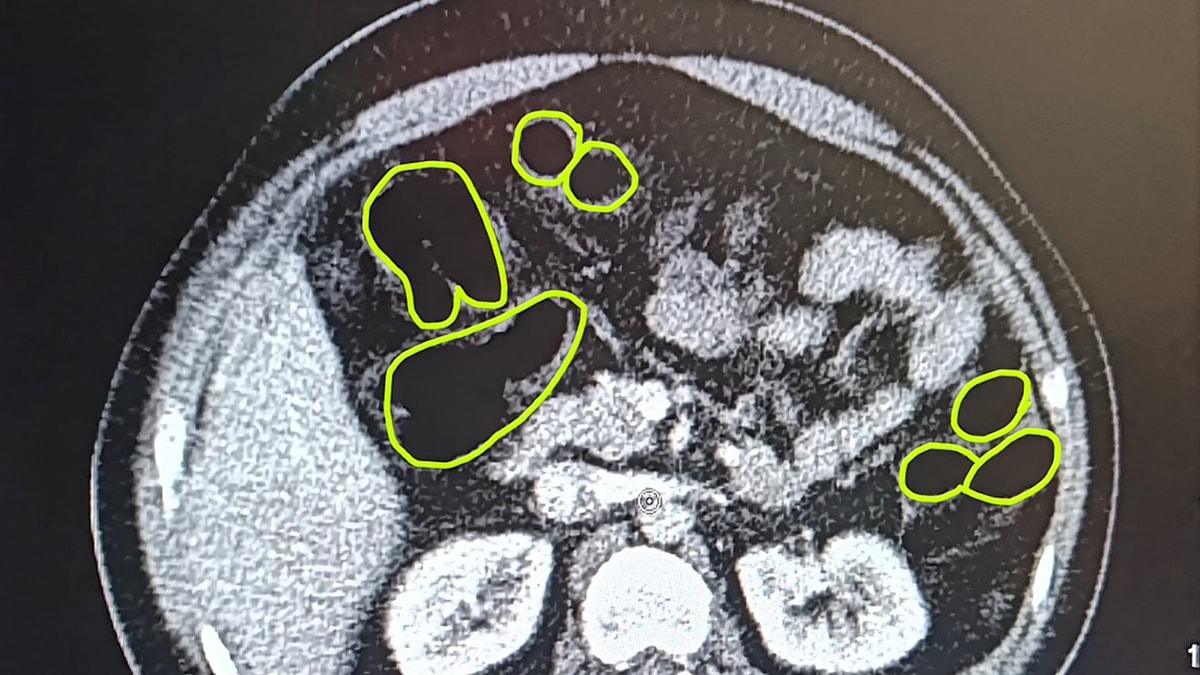

Alınan bilgiye göre jandarma ekipleri, İran uyruklu 51 yaşındaki A.O., 37 yaşındaki M.S. ve 28 yaşındaki P.S..'nin ülkelerinden kente uyuşturucu getireceği bilgisi üzerine harekete geçti. Şüpheliler Kocasinan ilçesi Himmetdede Mahallesi'nde taksi ile kente girmek istediği esnada durduruldu. Jandarma ekiplerince araçta yapılan aramada 15 gram esrar, 5 gram bonzai ve 117 adet uyuşturucu hap ele geçirildi. Gözaltına alınan 3 şüpheli muayene olmak üzere Kayseri Şehir Hastanesi'ne getirildi. Röntgen ve ultrason sonrası kontrollerde 3 şüphelinin midesinde uyuşturucu madde olduğu belirlendi. Şüphelilerin yuttukları uyuşturucuları kente sokmaya çalıştıkları tespit edildi. Kapsüller, sağlık ekibinin müdahalesiyle çıkarıldı. Taburcu edilen şüpheliler, İlçe Jandarma Komutanlığı'na götürüldü